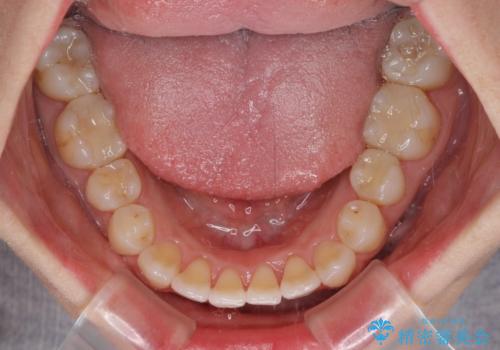

下顎前歯の叢生が顕著な場合、歯列改善後に歯と歯と歯肉の間にブラックトライアングルという隙間ができてしまいます。

軽減することはできますが、完全に解決することは矯正治療のみでは不可能なため、リスクとして事前に周知しておく必要があります。